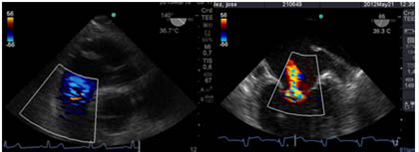

Por convención , el doppler espectral resultante muestra la velocidad en el eje de la Y y el tiempo en el eje X. El flujo que se dirige hacia el transductor, aparece por encima de la línea de base, mientras que el flujo que se aleja, se encuentra por debajo de la línea de base. El Doppler Color, (Figura 9) es una variedad de Pulsado que utiliza una escala de colores, representada, en el flujo laminar, con rojo (flujo que se acerca al transductor) y con azul el que se aleja. Cuando el flujo se hace turbulento, debido a una alteración funcional de la válvula, aparecen los colores amarillo y verde, reflejo de un aumento en la velocidad de la sangre al cruzar una válvula patológica anatómica o funcionalmente(13). (Figura 10)(Figura11)

Figura 11: Izquierda: flujo turbulento por insuficiencia pulmonar leve. (TG profunda TSVD). Derecha: imagen a 66° medioesofágico 2 cámaras flujo turbulento por insuficiencia mitral moderada.

Luego con Doppler Color, analizamos la dirección del chorro regurgitante que es opuesta a la valva comprometida, el tamaño del jet regurgitante y su relación con el área de la aurícula izquierda (AI). Debemos tener en cuenta que el mapeo color del chorro regurgitante está influenciado por parámetros del ecógrafo: ganancia, PRF, límite de Nyquist, y por parámetros fisiológicos: presión arterial, volemia.

Otro factor que afecta el tamaño del chorro es la dirección de éste, los centrales en la aurícula aparecen más grandes con Doppler Color, que aquellos excéntricos que corren sobre la pared auricular, generando un efecto coanda (Figura 15), con un volumen regurgitante muy similar y que por su sola presencia le confiere severidad.

Figura 15 imagen de 4 cámaras medioesofágico con insuficiencia mitral severa, observada con Doppler color (escala 64) con efecto “coanda”, reflujo hacia la pared de AI.

Clasificamos la IM en leve si el área del jet es < 4cm2, o <20% del área de la AI; moderado de 4-8cm2 y severo mayor de 8cm2.